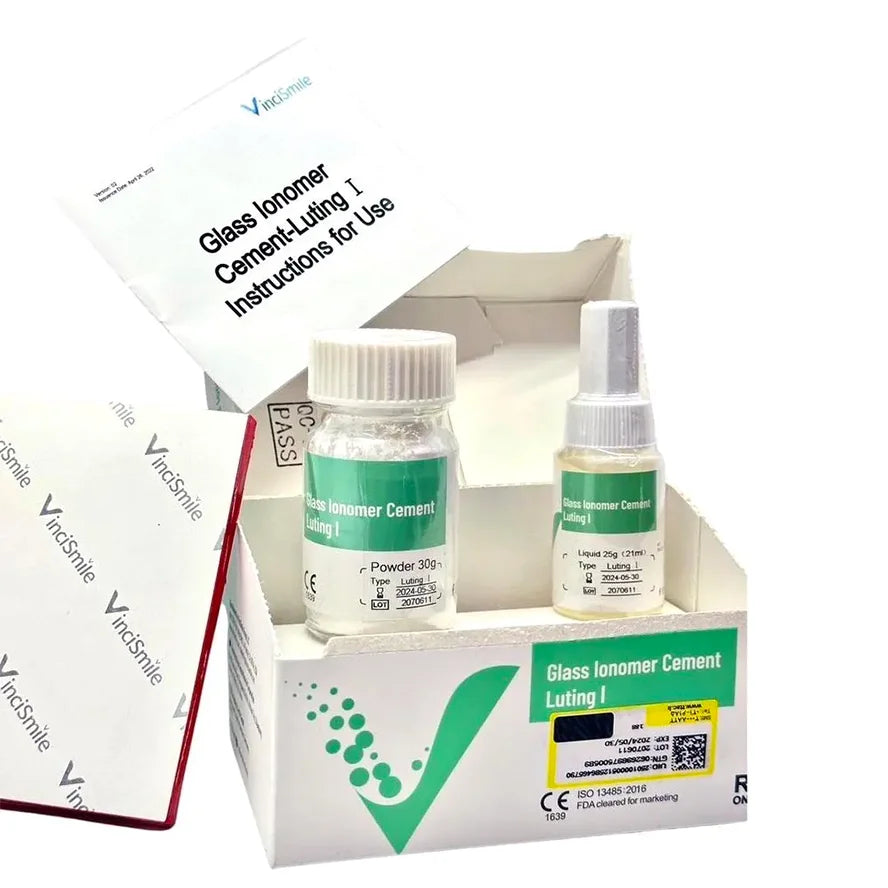

Glass Ionomer Cement Luting I - VINCISMILE

Standard: 30g × 1 powder + 25g × 1 liquid + 1 measuring spoon + 1 mixing pad (50 sheets)

Mini: 10g × 1 powder + 10g × 1 liquid + 1 measuring spoon + 1 mixing pad (50 sheets)